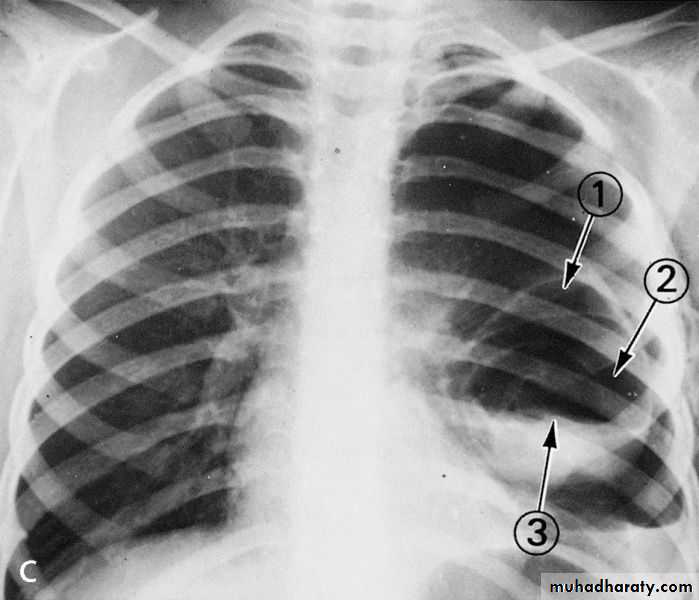

X-ray of pleural effusion

X-ray pneumothorax